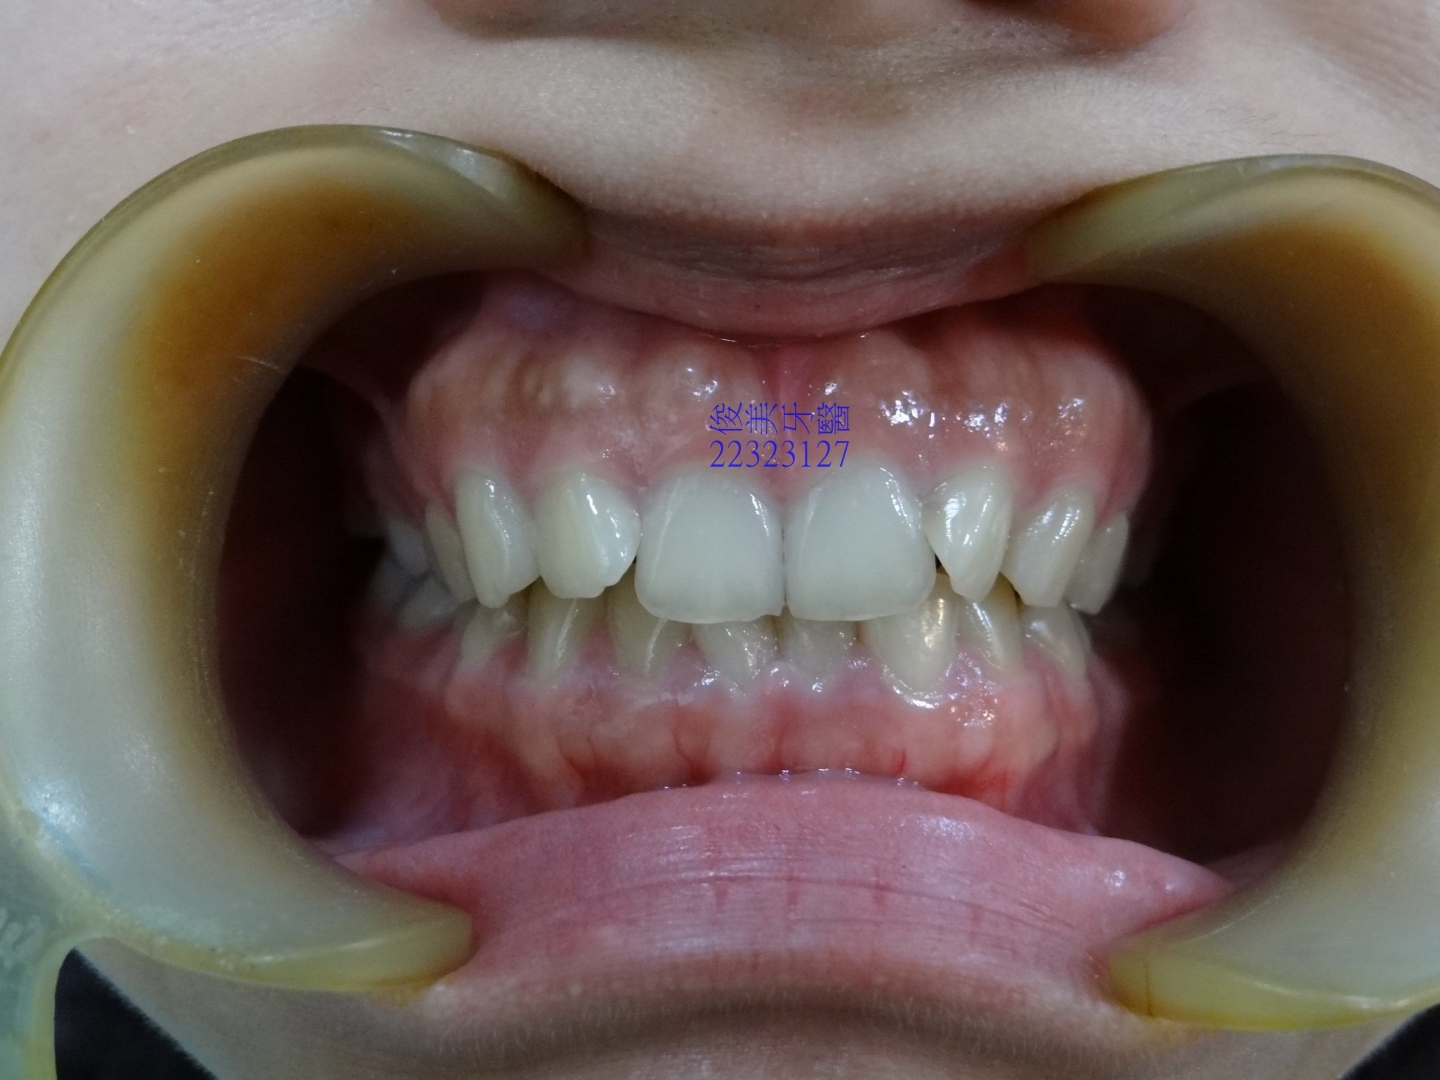

![]() 患者於門診中表示,牙齒很擁擠,想要改善;經醫師門診後,建議患者進行矯正治療即可改善。 ![]() 牙齒重疊... ![]() 有深咬現象... ![]() 上顎狀況... ![]() 下顎狀況... ![]() 左側咬合,牙齒往舌側傾斜...... . ![]() 右側咬合,牙齒往舌側傾斜...... ![]() 治療中....擁擠和深咬已改善.... ![]() 牙齒往後移.....將牙齒齒軸回正一點。 ![]() 治療結束,拆除矯正器了............. ![]() 患者好開心......牙齒整齊後,笑容更可愛了。 ![]() 也沒有暴牙的狀況。 ![]() 上顎牙弓狀況。 ![]() 下顎牙弓狀況。 ![]() 右側咬合狀況。 ![]() 左側咬合狀況。 ![]() 已拆除超過5年,依舊配戴維持器,保持最佳狀態。 |